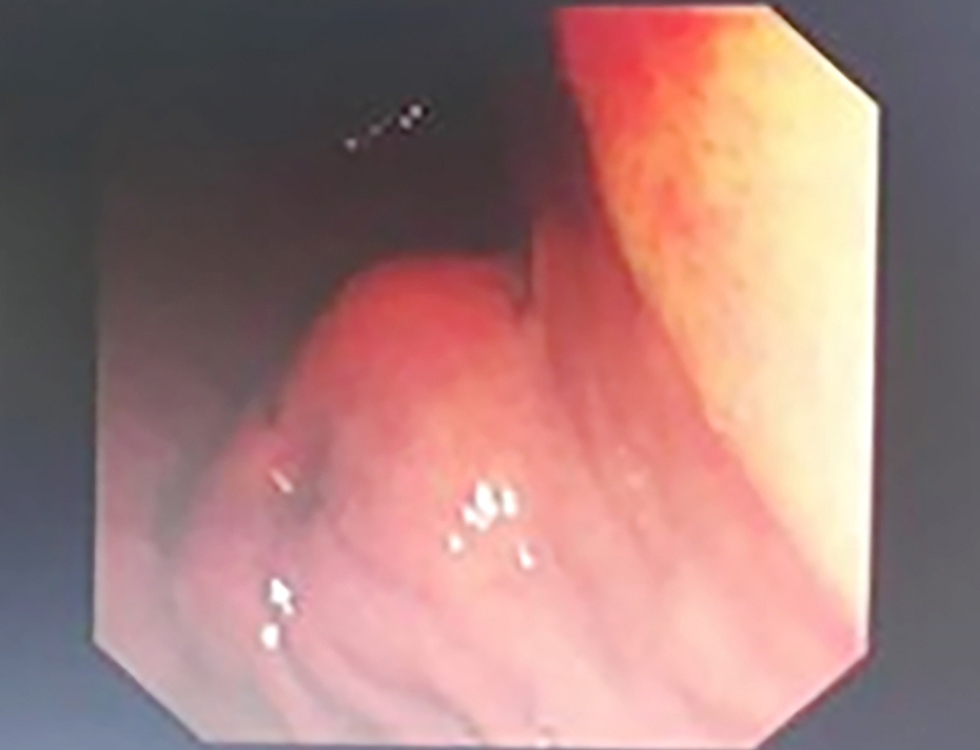

Figure 2 - Endoscopic view of the gastric antrum: Endoscopic image showing the gastric mucosa with potential submucosal lesion suspicious for GIST. (SCV: Scope Channel View; C:N Br:A1 G:O refers to endoscopic coordinates and settings with C:N indicating Color/Normal mode, Br:A1 indicating Brightness level A1, and G:O indicating Gain/Offset settings)

Endoscopic examination revealed a submucosal, well-circumscribed mass lesion in the antrum of the stomach (fig. 2). This endoscopic appearance represents the typical presentation of our gastric GIST cases and similar endoscopic findings were observed in all gastric GIST cases.